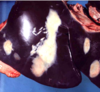

What infectious agent caused this hepatitis?

letpospirosis